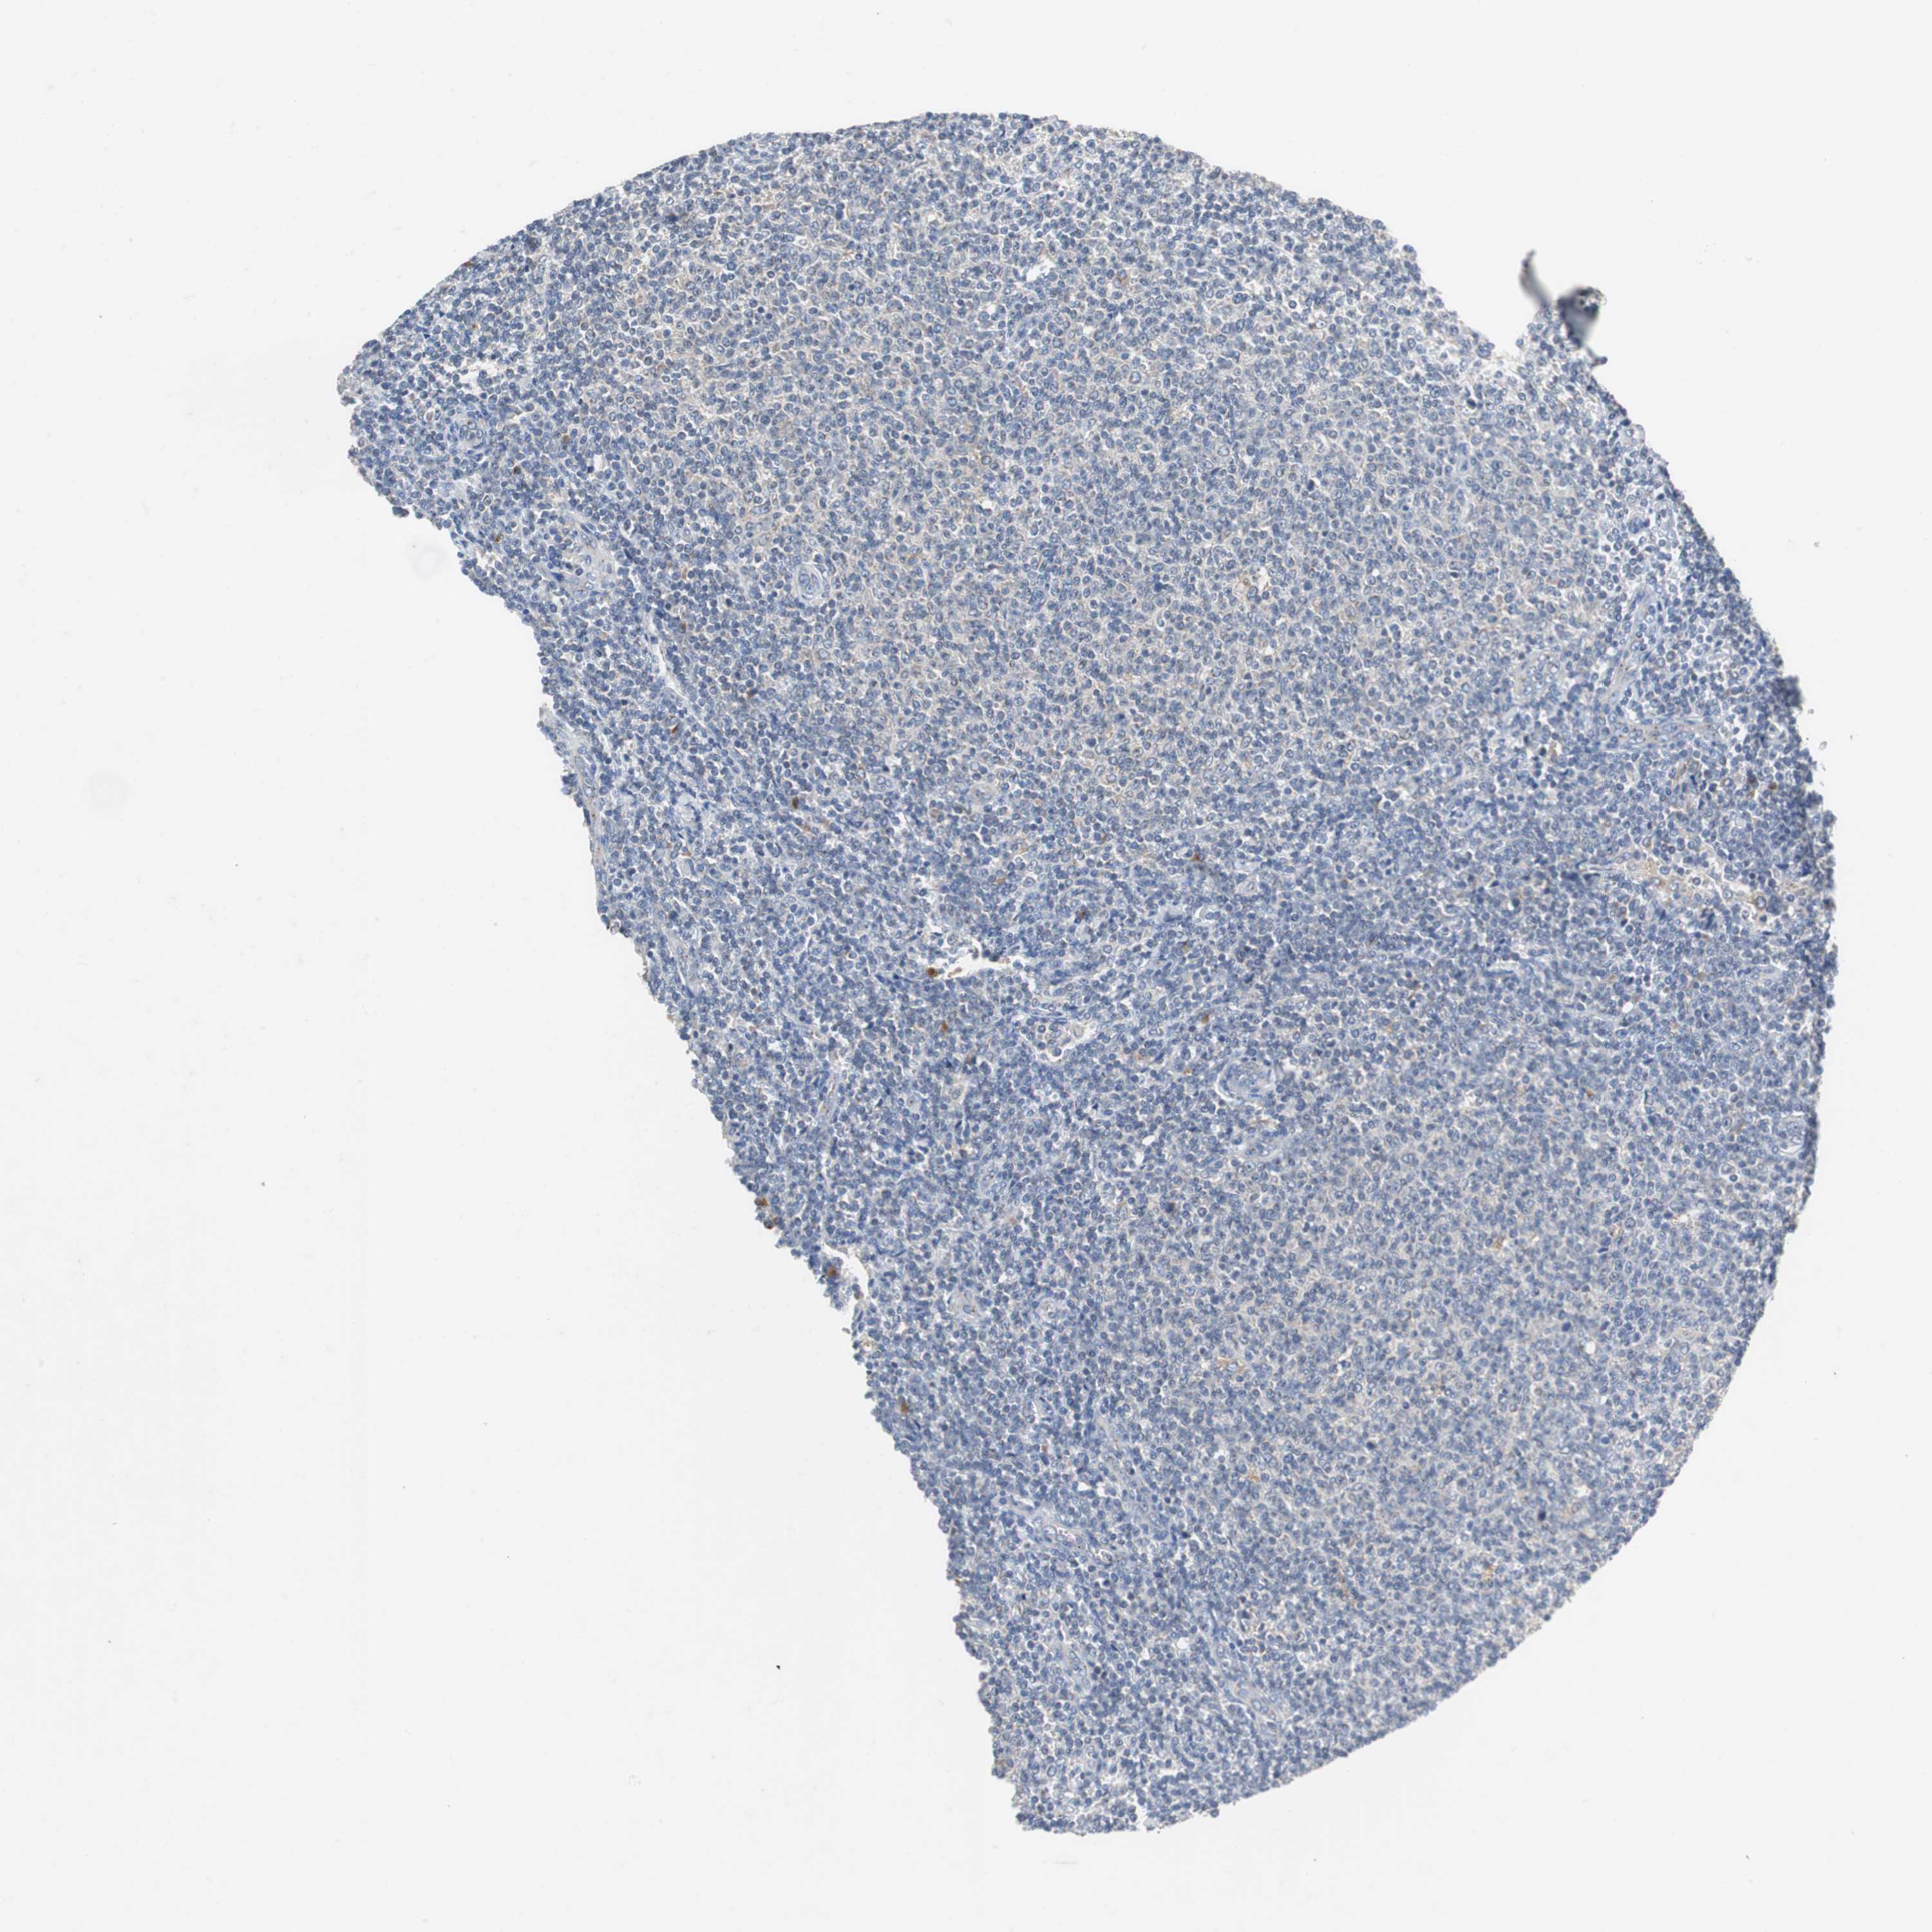

LYMPHOMA - Protein expressioni

A mouse-over function shows sample information and annotation data. Click on an image to view it in a full screen mode. Samples can be filtered based on level of antibody staining by selecting one or several of the following categories: high, medium, low and not detected. The assay and annotation is described here.

Antibody HPA007305

Staining

Not detected

Negative

None

Malignant lymphoma, non-Hodgkin's type, Low grade